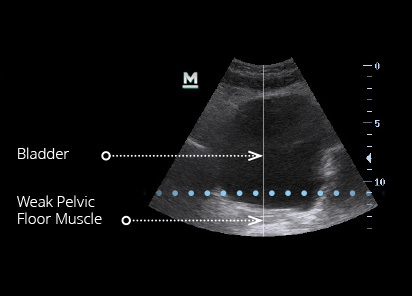

Ultrasound images of pelvic floor showing changes in muscle mass and muscle tone after the EMSELLA treatment.

Results and patient experience may vary.